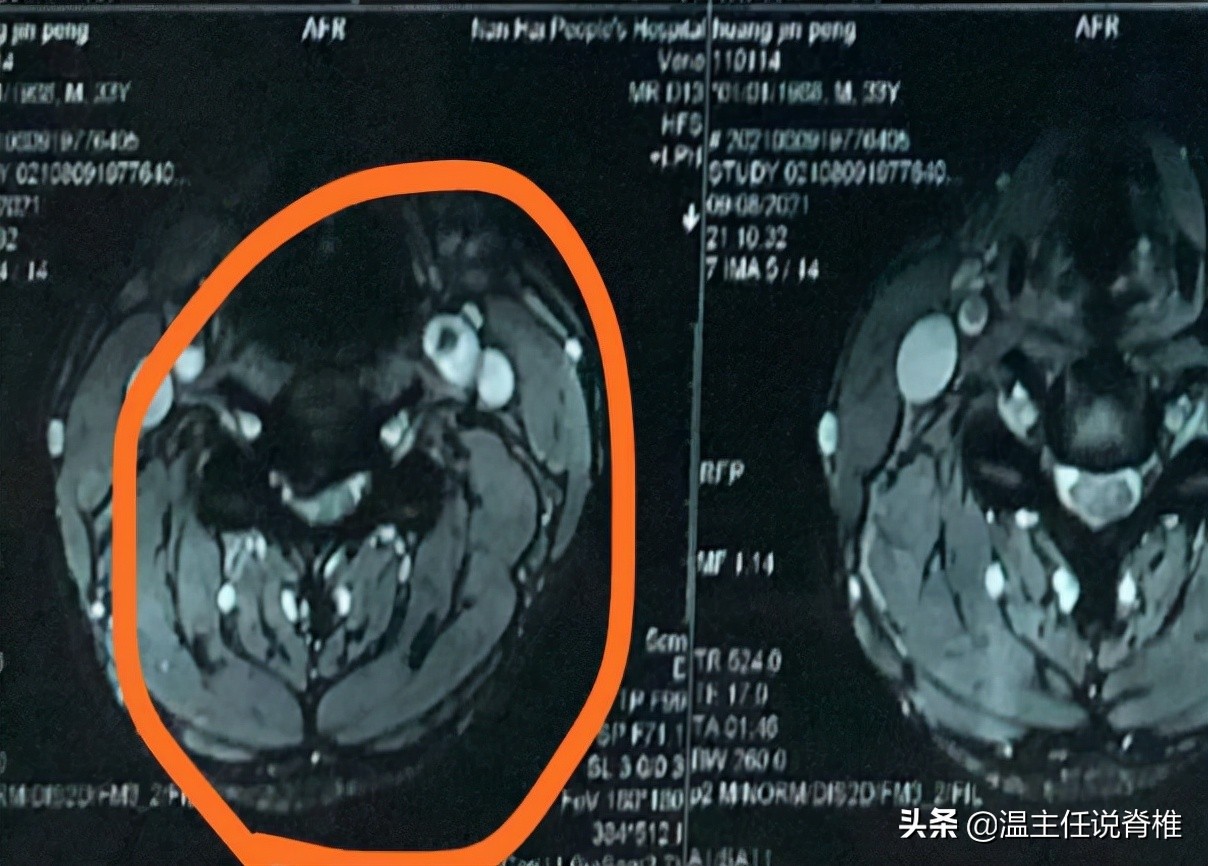

等到了今年8月份回龙脊康再做治疗时,病人描述自己左手手指出现麻木,右手和下肢麻木且出现乏力、踩棉花感,该症状已持续8-10天。我考虑到病人事隔多月,现已出现明显手麻的症状,为了安全起见,建议他去外院重新拍颈椎MR。在外院医生重新检查后,他的颈椎出现脊髓受压变性,霍夫曼征呈阳性。

脊髓受压变性

霍夫曼征阳性